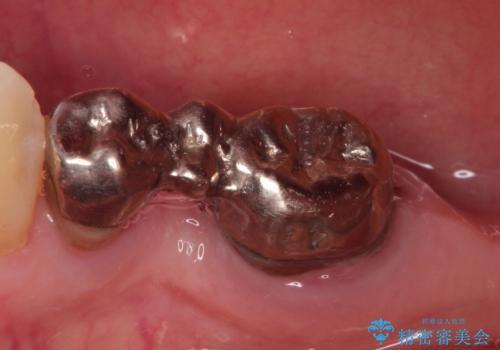

右上のかぶせ物がとれてしまい、残った根っこも虫歯になってしまっていました。

また右下の歯も虫歯と歯周病により長く使用するには難しい状態でした。

右の上下の歯を抜歯してインプラントを埋入して、かぶせ物を装着する計画としました。